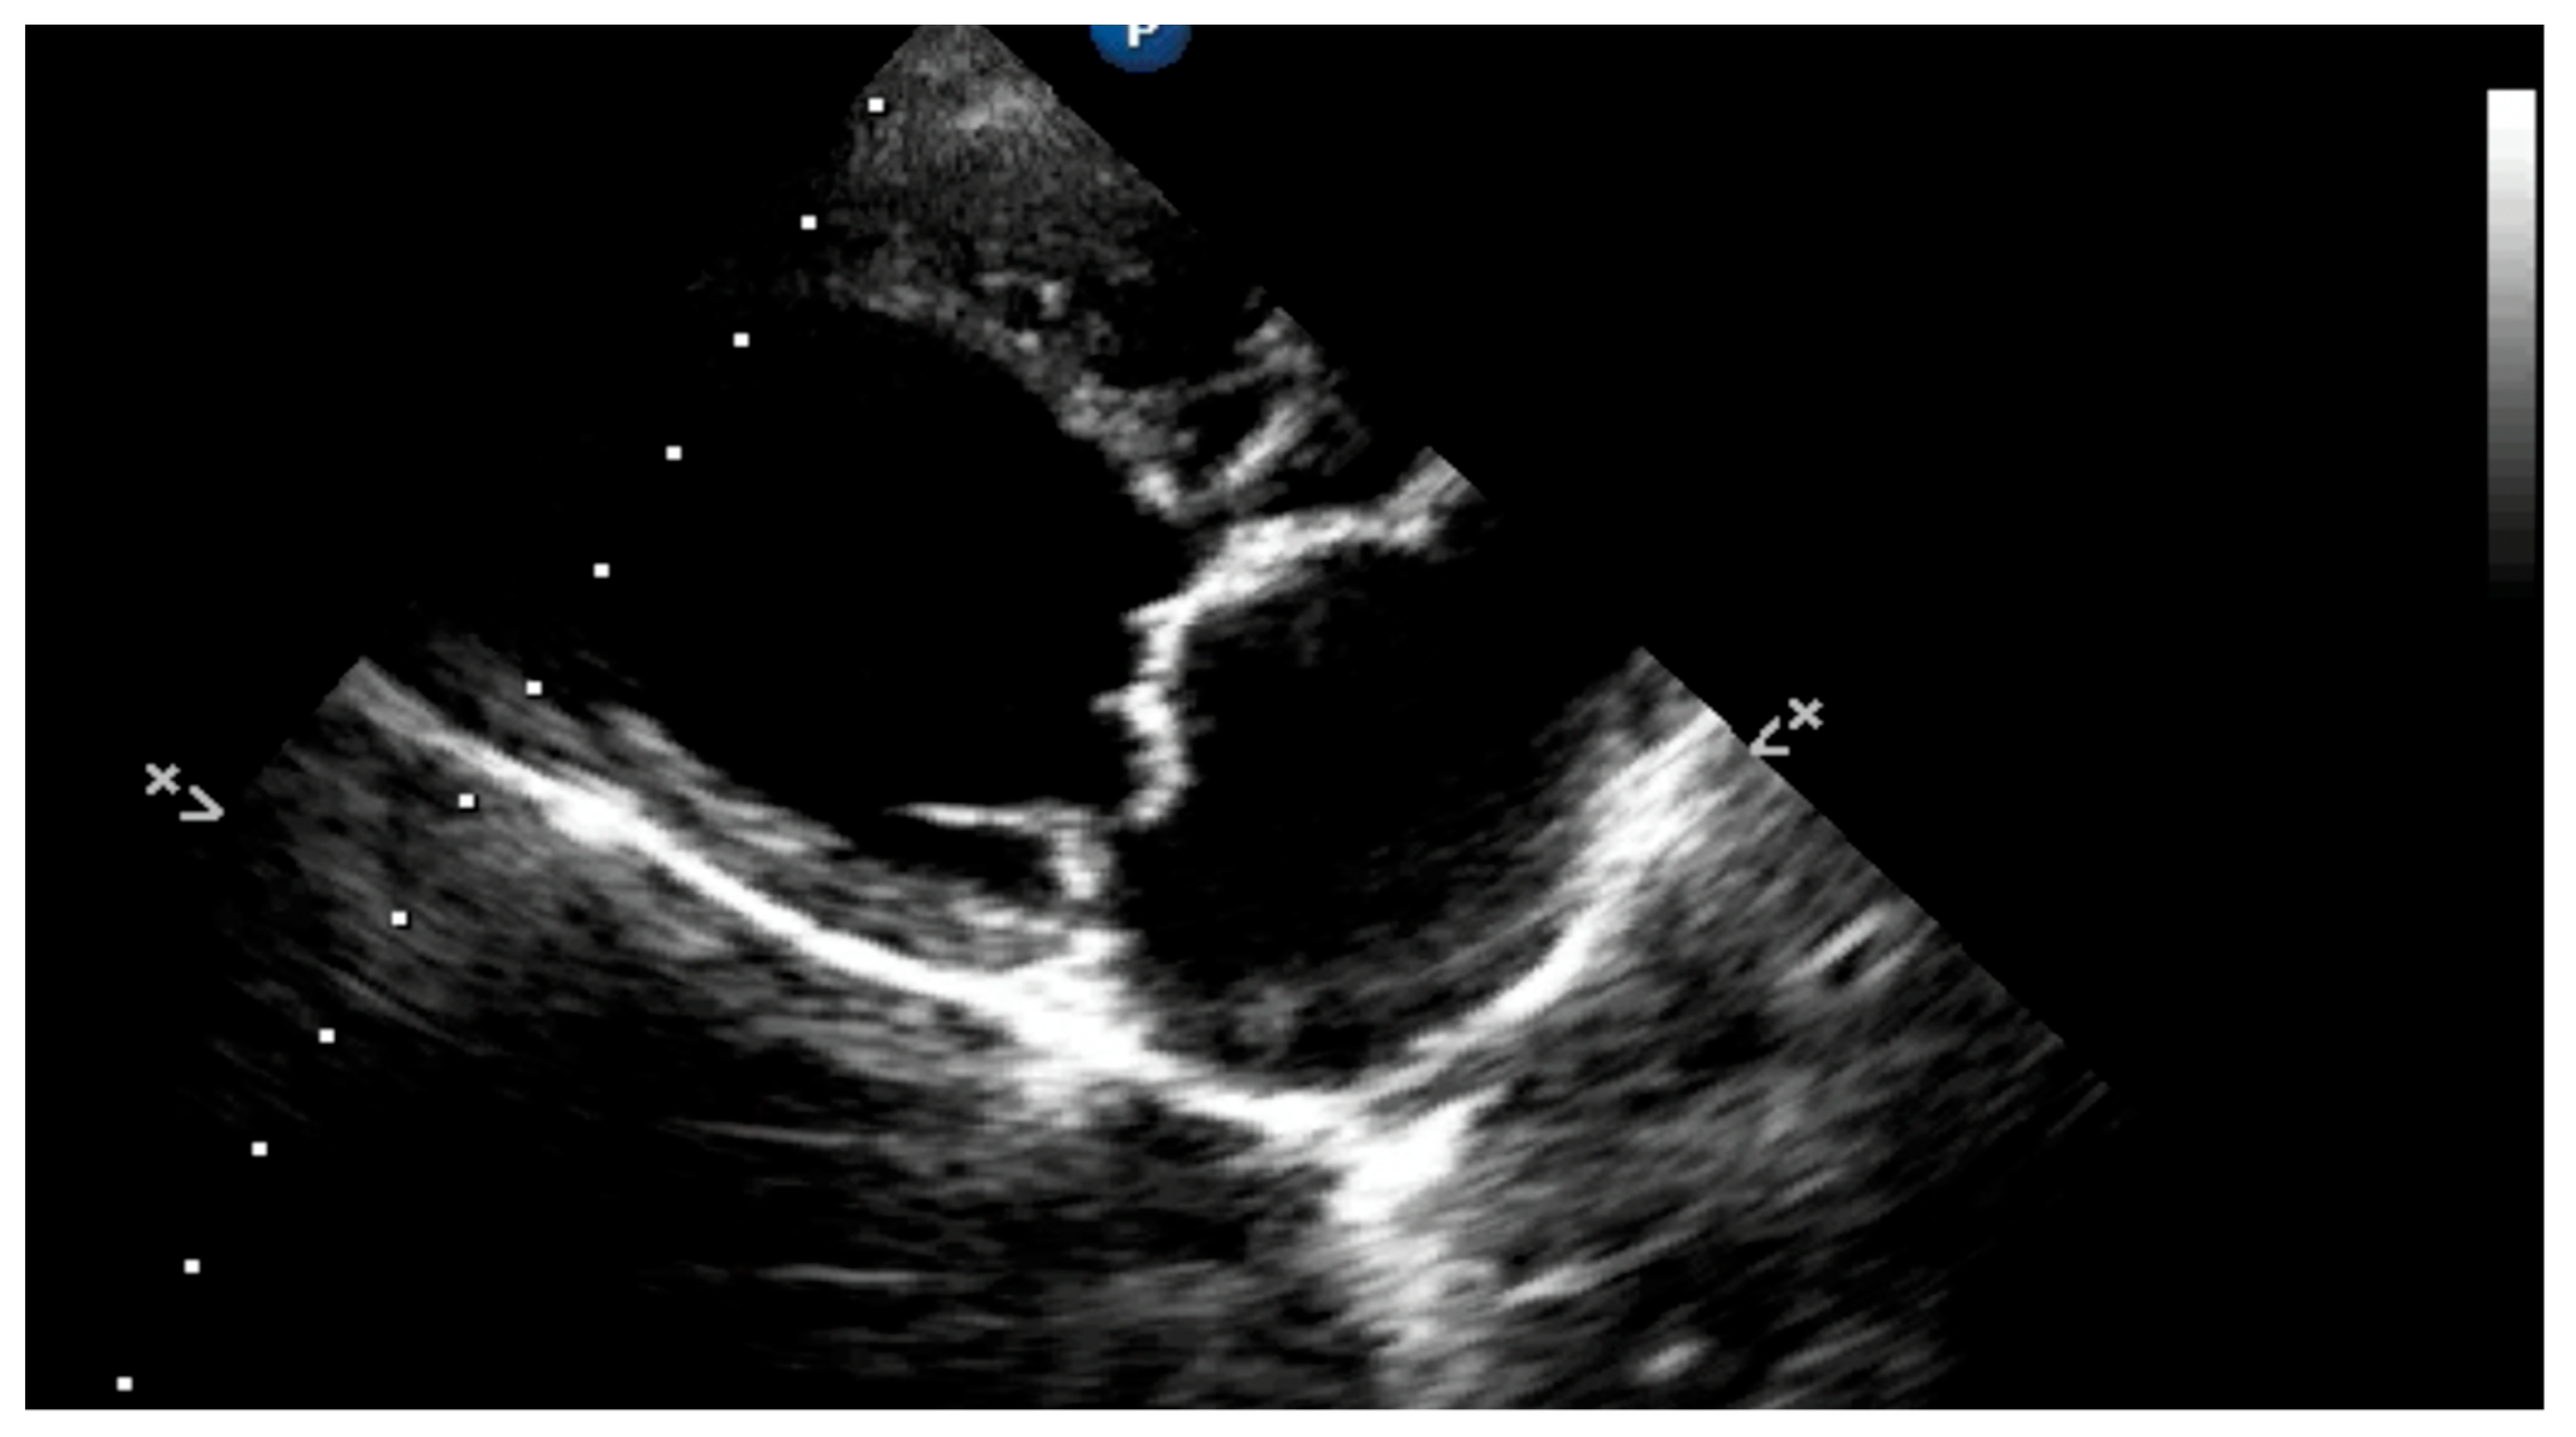

4.8.2. Presence of Vena Contracta

4.8.3. Degree of Myxomatous Degeneration